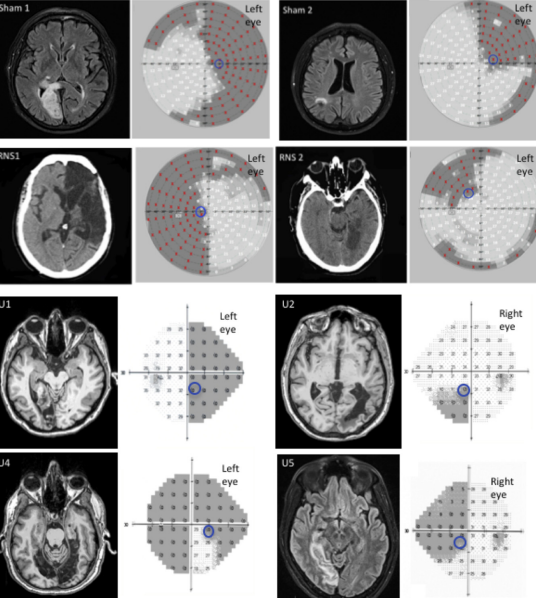

This double-blinded study monitors the effect of visual training and noninvasive brain stimulation (tRNS) on the visual recovery of those with visual field deficits from cortical damage. Baseline measures such as visual perimetry tests, EEG, fMRI and visual discrimination tasks are compared immediately after 10 days of daily sessions and then 3 months after. There is a 50% chance the participant will receive "sham" stimulation, or no stimulation, and neither the participant or researcher will know until the entire study has completed.